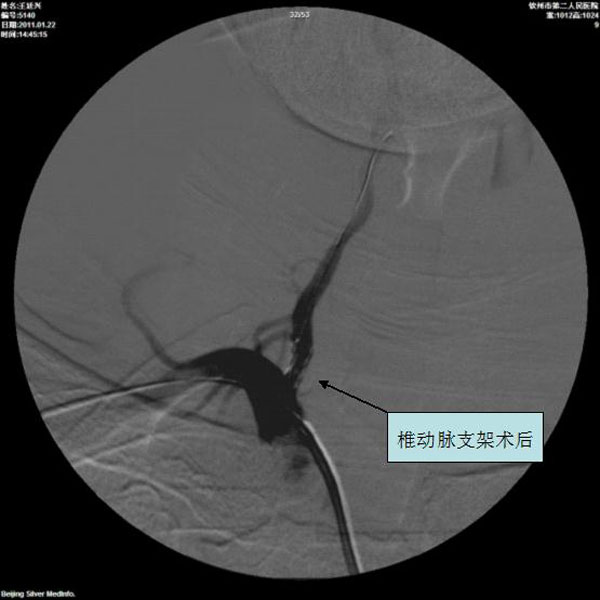

椎动脉支架术前

椎动脉支架术后